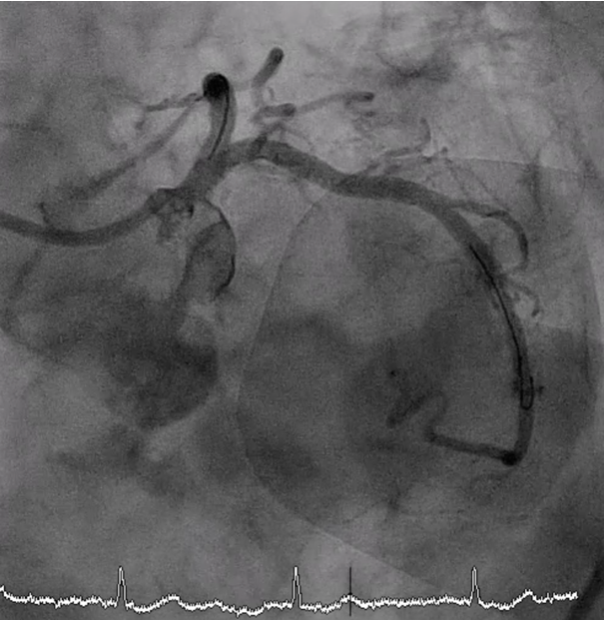

A 7 Fr JL 4.0 guiding catheter was engaged into LCA via RFA. We planned to perform PCI at LM bifurcation with Culotte technique. We successful wired to distal LAD using Finecross microcatheter with Conquest Pro guidewire (Failed using Sion blue, Fielder XT and Gaia Next2 guidewires). The microcatheter could not pass LAD lesion. Successfully passed the lesion using Tornus microcatheter. Then we exchanged RotaWire Floppy wire. Rotational atherectomy was done at LM-proximal LAD with Burr 1.25 mm at 180,000 rpm total 2 runs and step up Burr to 1.75 mm at 180,000 rpm total 2 runs for further debulking. Then we wired to LAD with Sion blue and LCx with Sion guidewires. IVUS was performed in LM, LAD and LCx. IVUS from LM-LAD showed eruptive calcified nodules with cracked calcific plaques and reverberation with MLA 2.86 mm2. IVUS from LM-LCx showed MLA 4.6 mm2. We prepare the lesion LM-LAD with non-compliant 4.0/15 mm balloon at 20 atm. A 4.0/18 mm stent was deployed from LM to LAD then re-wiring. We prepare the LM-LCx with semi-compliant 2.0/15 mm balloon (for opening strut) at 14 atm, 2.5/15 mm balloon at 14 atm and non-compliant 4.0/15 mm balloon at 20 atm. A 4.0/23 mm stent was deployed from LM to LCx. The KBI was performed with non-compliant 4.0/15 mm balloons at 10 atm. POT was performed with non-compliant 4.0/15 mm balloon at 14 atm. Final angiogram showed good coronary blood flow and IVUS demonstrated well stent expansion, no malapposition and no stent edge dissection.